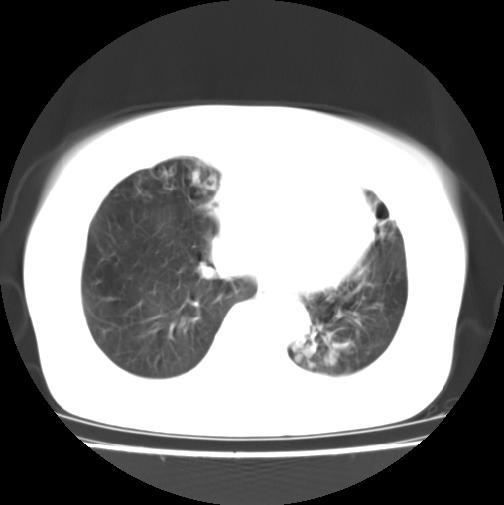

女性病人,56岁,反复咳喘30余年,伴大量脓痰,偶有痰中带血。

此病例在科室里有较大的争议,我认为是先天性肺囊肿(理由是:两者起病年龄都较轻,都有咯血及脓痰的症状,而先天性肺囊肿壁薄;而支扩的囊腔旁一般都能看到伴行的血管影,形成“印戒”征)。以上为个人的意见,请高手们指点一下。

支持支气管扩张并感染,肺囊肿一般有较完整的囊壁。。。

影像符合支气管扩张伴感染,先天肺囊肿壁薄,而后天支扩因反复感染壁多较厚,有慢性支气管炎病史。最后诊断靠病理,先天肺囊肿的囊内无尘埃。

本例应为支气管扩张并感染,与囊肿区别在于其大小,分布,壁改变,与肺动脉关系,形态等来鉴别,要点大家都说得差不多了,囊肿要大些,分散些,靠外围一些,而支扩靠内一些,聚拢些,小一些且易聚拢呈葡萄状,不能单从囊壁厚度来评价,特别是有粘液栓类的改变更加支持支扩,有时支扩亦与囊肿混在一起并存.个人意见仅供参考.